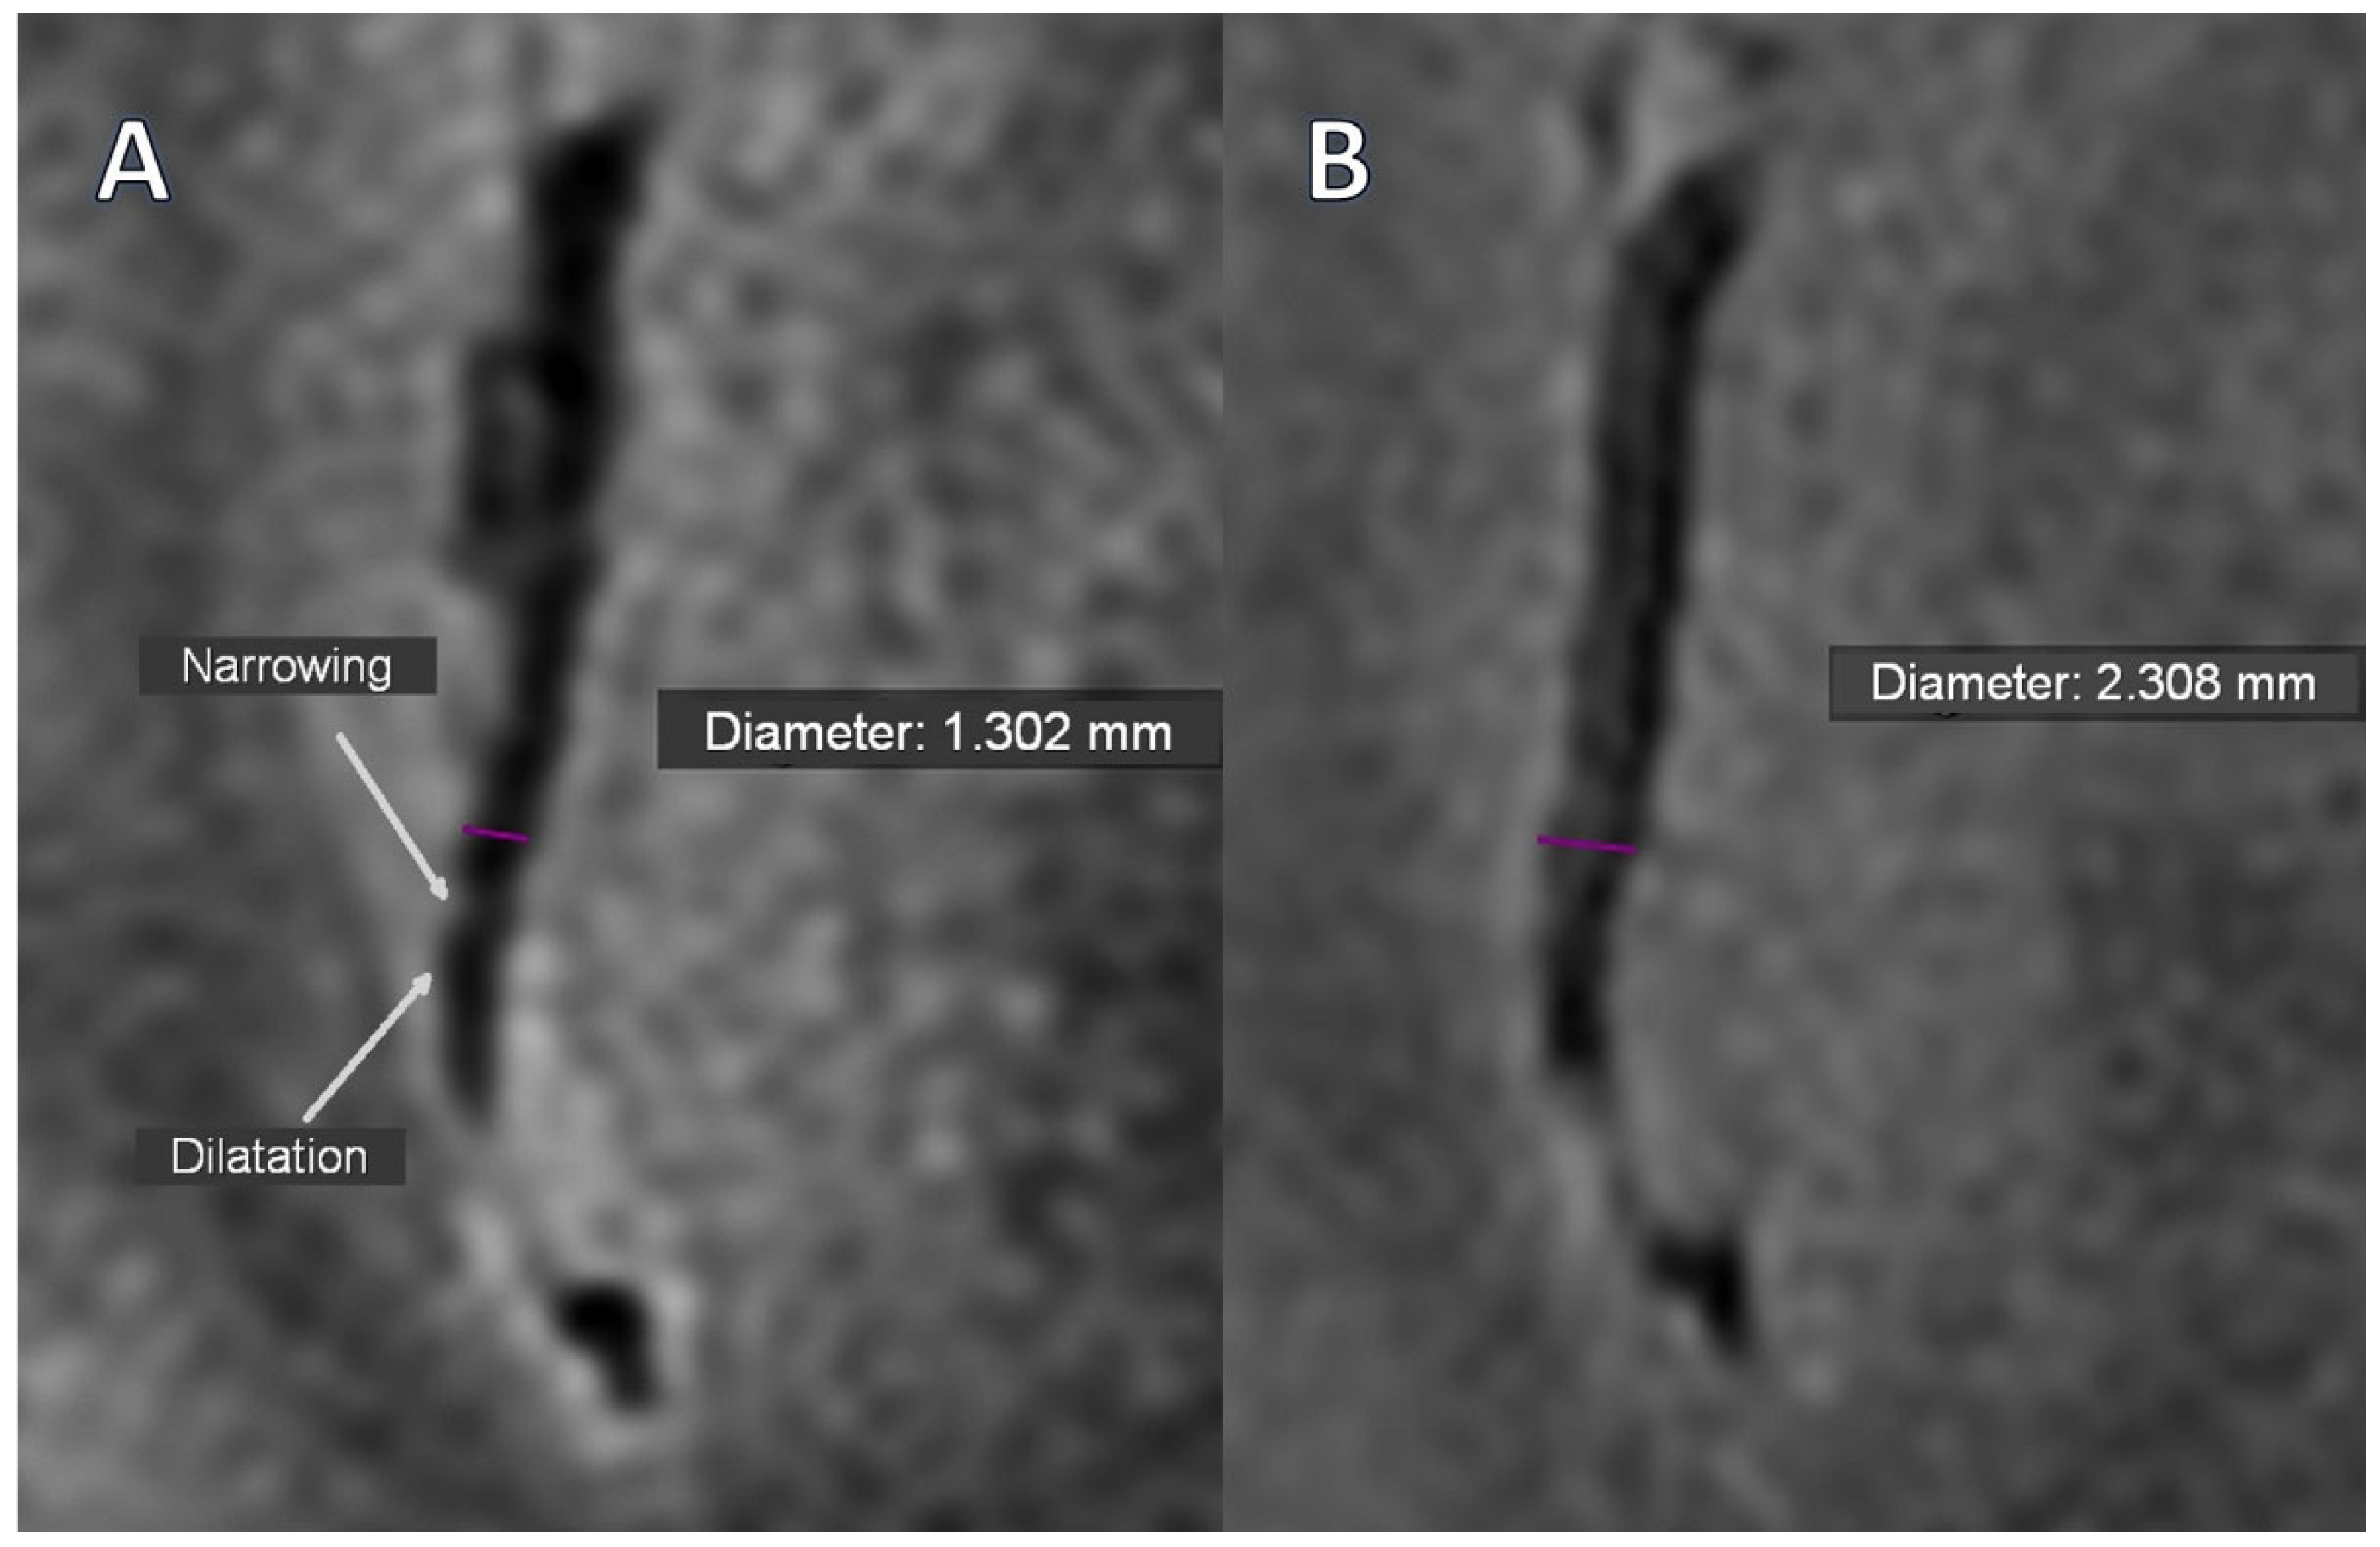

Only two segmental arterial narrowing in secondary vascular branches were investigated in Stage 0 TOF, which were absent in Stage 1 (Table 3). However, this change was not substantial. The occurrence of VAND in secondary as well as in tertiary vascular branches was initially detected in the BB sequence in 37.9% of patients, with their reduction to 17.2% (p = 0.031) and 10.3% (p = 0.008) in Stage 1, respectively (Figure 1A,B, Figure 2A,B).

Figure 1. The intracranial vessel in BB STIR T2 axial sequence; Purple—diameter; (A)—Alternating narrowing and dilatation (white arrows) visible before treatment; (B)—Normalization of vessel lumen after treatment (Stage 1).